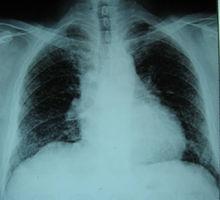

1、胸片 PLCH早期,胸片表現為雙肺邊界不清的微結節或網結節浸潤,以中上肺為著,肋膈角通常不受累(圖4a)。囊狀改變是疾病特徵性的改變,可以與結節同時存在。PLCH終末期,可見多個直徑在2cm以上相鄰的囊腔,不易與肺氣腫或淋巴管平滑肌瘤病(LAM)相鑑別。PLCH胸片可見氣胸,極少數病例可見肋骨的溶骨性損害。胸腔積液和肺門淋巴結腫大罕見。合併肺動脈高壓時,胸片示右下肺動脈乾增寬,肺動脈段膨隆,以及右心室擴大(圖4b)。少數早期患者(<10%)胸片正常。

1、戒菸 戒菸是首要的治療措施,50%~75%的患者在戒菸後6~24個月病情穩定或好轉,症狀緩解,影像學病變部分或完全消失(圖8a,b)。同時,戒菸也可以減少罹患肺癌、慢性阻塞性肺疾病、心腦血管疾病的風險。